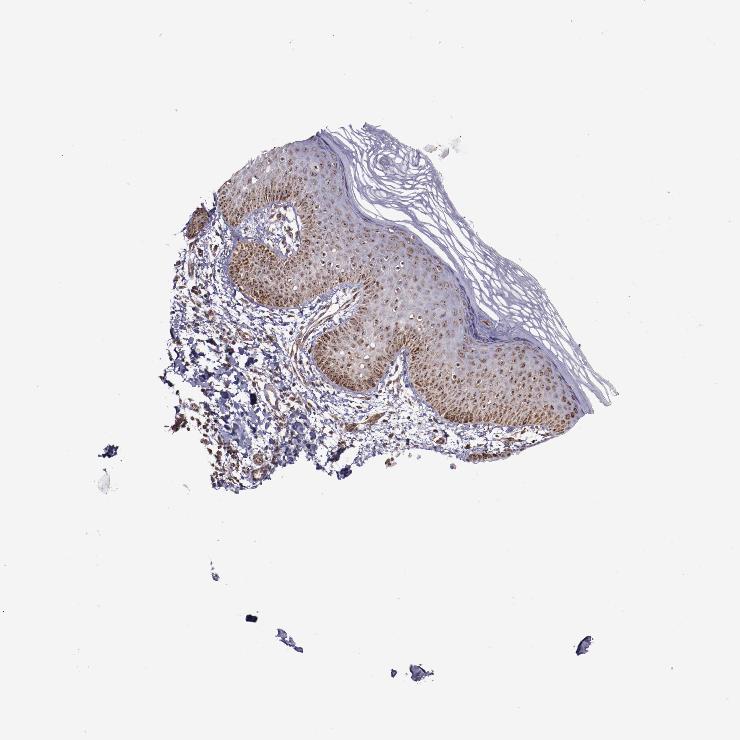

SKIN 1 - Antibody stainingi

Antibody staining in the annotated cell types in the current human tissue is reported as not detected, low, medium, or high, based on conventional immunohistochemistry profiling in selected tissues. This score is based on the combination of the staining intensity and fraction of stained cells.

Each image is clickable and will lead to virtual microscopy that enables deeper exploration of all samples and also displays staining intensity scores, fraction scores and subcellular localization as well as patient and tissue information for each sample.

Antibody HPA002192

Langerhans Medium

Fibroblasts Low

Keratinocytes High